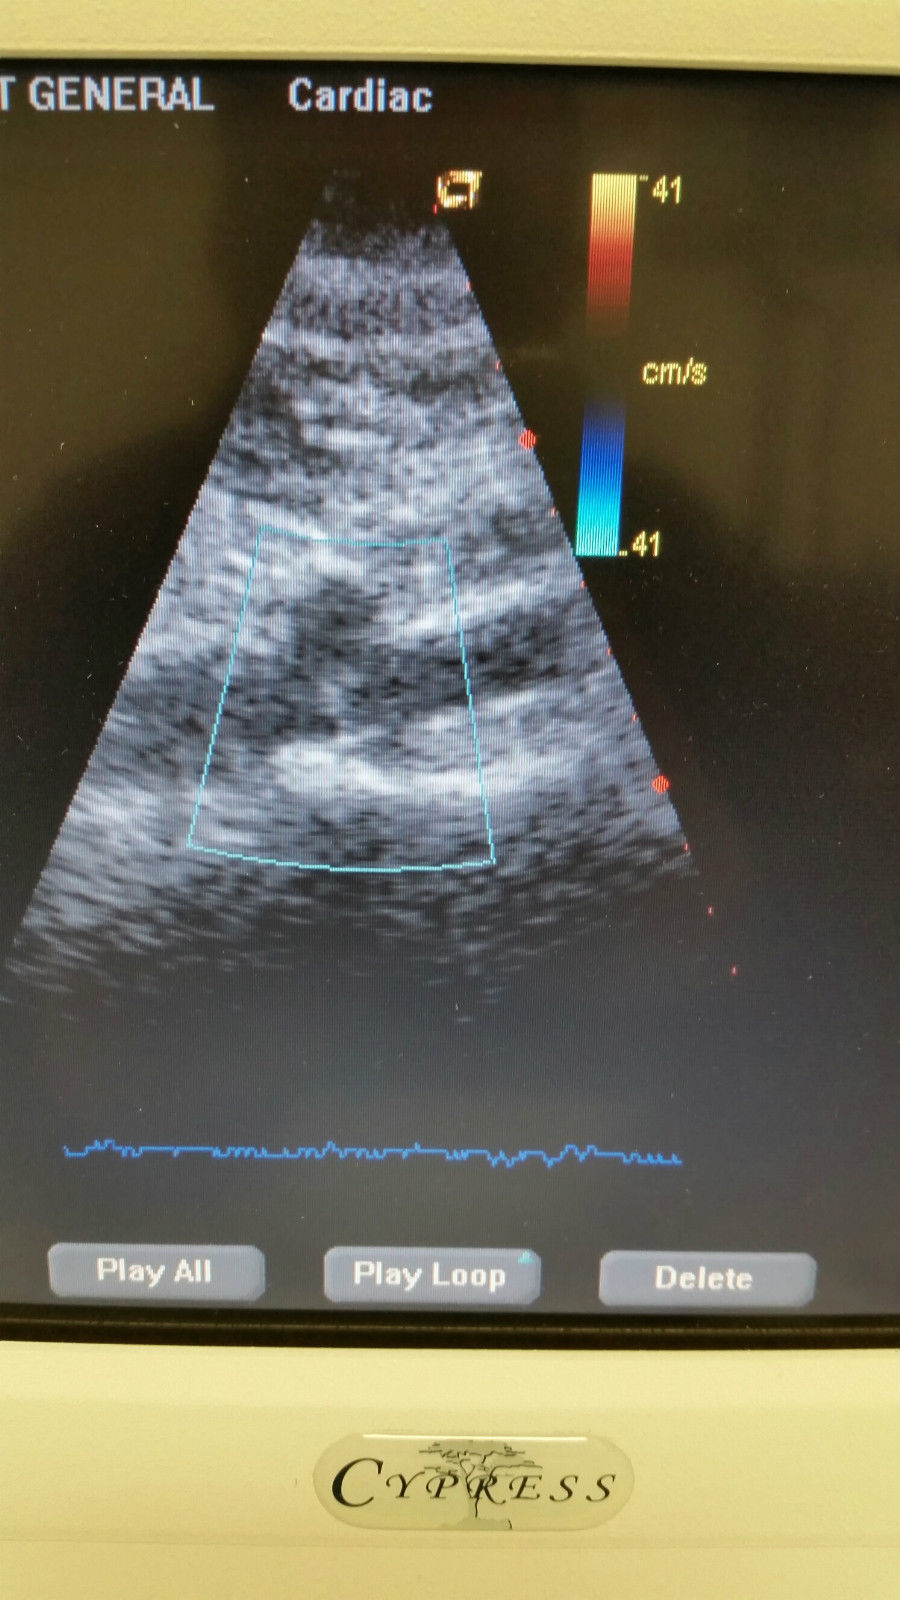

The Acuson Cypress Cardiac Vascular Ultrasound Machine is engineered for exceptional imaging and diagnostic accuracy. Its advanced technology allows for detailed visualization of cardiac and vascular structures, which is essential for healthcare providers. The inclusion of the 3V2c and 7L3 probes enhances its versatility, making it suitable for various clinical applications. As a result, this machine is a crucial tool in modern cardiology and vascular assessment.